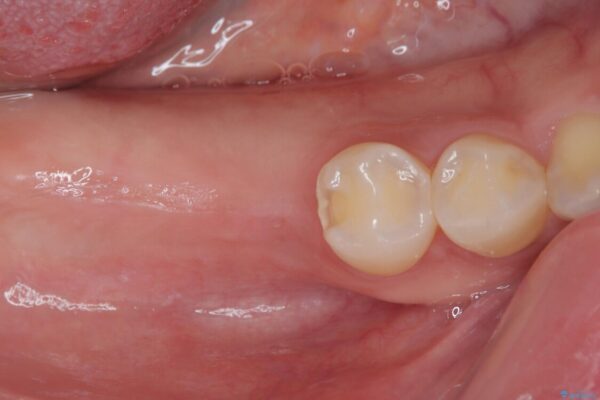

そこで、右上の奥歯に部分的なワイヤーを装着し、さらに矯正用アンカースクリュー(TADs)を併用することで、挺出した歯を圧下(歯を元の高さに戻す動き)させ、下顎にインプラントを埋入するための十分な垂直的スペースを確保しました。

→ この装置は部分的な矯正で、前歯など見える位置にワイヤーがかかることはなく、見た目を気にすることなく、普段通りの生活を送りながら治療を進めることができました。

治療途中

• 挺出歯を圧下してスペースを確保!目立たない部分矯正で下顎大臼歯にインプラント治療を実現 治療途中画像